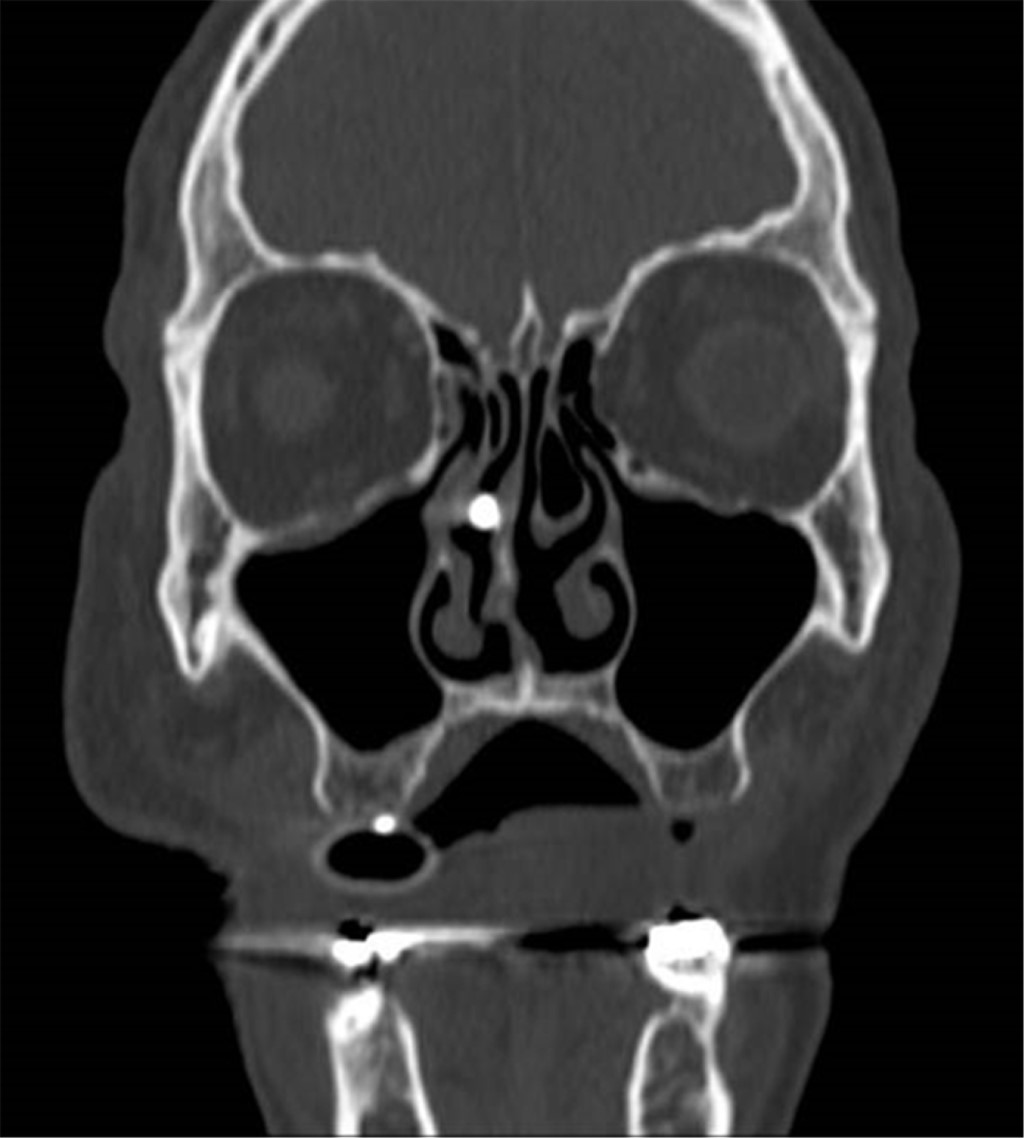

Paciente masculino de 69 años de edad con historia de diabetes mellitus tipo 2 en tratamiento con metformina y clorpropamida, hipertensión arterial en tratamiento con losartán y amlodipino. Se presenta al servicio de urgencias por mostrar cefalea, dolor torácico, tos, mialgias, artralgias y disnea de una semana de evolución. A su ingreso muestra frecuencia cardiaca 114 lpm, frecuencia respiratoria de 24 rpm, saturación de oxígeno de 80% sin apoyo de oxígeno suplementario, glucosa 587 mg/dl, leucocitos de 25,690 cel/mm3, neutrófilos 85%, linfocitos 1.2%, hemoglobina 16.3 g/dl, procalcitonina 3.78 ng/dl, gasometría arterial con pH 7.41, pCO2 21 mmHg, PO2 35 mmHg, HCO3 13 mmol/l, saturación de oxígeno 62%. Se realiza prueba rápida de antígeno para SARS-CoV-2 resultando positiva, tomografía axial computarizada (TAC) de tórax en la que se observan datos radiológicos sugestivos de infección por SARS-CoV-2 (Figura 1), se inicia manejo con oxígeno suplementario, bomba de infusión de insulina, carbapenémicos, antihipertensivos, dexametasona y profilaxis antitrombótica con enoxaparina. A las 48 horas de su ingreso continúa con choque séptico, se inician aminas vasopresoras, se realiza intubación orotraqueal y soporte con ventilación mecánica invasiva, se coloca sonda nasogástrica (SNG), la cual 24 horas posterior a su colocación reporta hematemesis acompañada de distensión abdominal, leucocitosis de 40,000 cel/mm3, se realiza TAC abdominopélvica simple, la cual revela neumatosis gástrica y neumoperitoneo (Figura 2), se efectúa laparotomía exploradora urgente encontrando necrosis de la curvatura mayor del estómago, se lleva a acabo gastrectomía vertical con engrapadora GIA cartuchos morados de 45 y 60 mm (Figura 3), se refuerza línea de grapeo con sutura continua prolene 00, se coloca sonda de yeyunostomía de alimentación a 60 cm del ángulo de Treitz y se dejan drenajes tipo Saratoga. A las 24 horas postoperatorias paciente reporta estabilidad hemodinámica y se suspenden aminas vasopresoras, se inicia nutrición enteral con dieta elemental. El quinto día postquirúrgico muestra adecuada tolerancia a dieta enteral por yeyunostomía, se realiza prueba con azul de metileno por SNG sin evidencia de fugas y descenso de leucocitos a 24,000 cel/mm3. Se recaba resultado de histopatología, el cual revela necrosis panmural asociada a trombosis arterial secundaria a microorganismos compatibles con Mucor sp., por lo que se inicia manejo con anfotericina B (Figuras 4 y 5). En el seguimiento muestra buena evolución, se realiza TAC abdominopélvica con contraste por SNG, la cual descarta fugas y colecciones intraabdominales y se corrobora integridad de la pared gástrica, se retiran drenajes y se da alta de cirugía general el día nueve postquirúrgico continuando manejo a cargo del servicio de medicina interna. Durante los siguientes días de hospitalización, el paciente presenta deterioro cardiovascular y pulmonar, se toma urocultivo, el cual evidencia crecimiento de Candida tropicalis, se realiza TAC de cráneo, tórax y abdominopélvica con contraste oral (Figuras 6 y 7), continúa sin evidencia de fugas a nivel abdominal, se descarta mucormicosis rinocerebral y pulmonar, se reporta probable neumonía bacteriana sobreañadida y neumopatía intersticial secundaria a COVID-19, persiste deterioro clínico y choque refractario, el paciente fallece a 29 días de su ingreso.

Figura 6